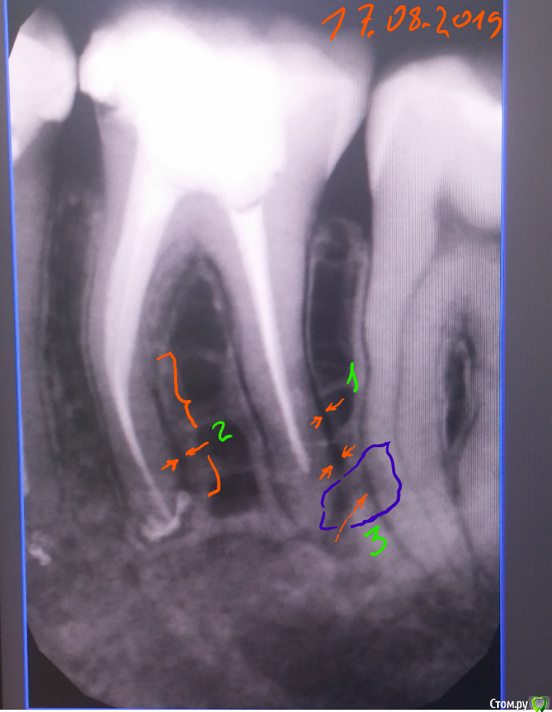

dentifree Опубликовано 19 августа, 2019 Поделиться Опубликовано 19 августа, 2019 Здравствуйте. !9.08.2019 заломило нижную челюсть в районе 6-го зуба.(слева). тупая непрерывная боль на весь день.В этот же день лечить не получилось. но удалось сделать прицельный снимок 6-ки.на второй день прошло.на третий день 11.08 опять заломило, + добавилась весьма сильная боль при накусывании на 6, и 7 зубы. на холод реакции не было., или была очень слабая.12.08. доктор поставил диагноз пульпит 6-го зуба, почищены каналы, после контрольного снимка, диагноз изменил на периодонтит. в этот же день поднялась температура до 38, на след.день спала.назначены антибиоткики,. сначала было улучшение. 6-ка и 7-ка перестали реагировать на накусывание.потом откатилось на ухудшение только 6-ки, но не на тот же уровень что до лечения.,появлялась температура в районе 37 -37,5после 5 дней, назначили еще один курс антибиотиков. на 19.08.2019 на накусывание по-лучше стало, но все-равно чувствительно, чуть ломит фоном в районе 6-ки, температура 37,5. Еще если двинуть челюсть влево->вбок, то ощущение будто что-то втыкается, боль от этого движения не сильная. верно ли диагноз поставлен ? и выбор лечения, ?его один раз вскрыли, запломбировали, и лечение только антибиотиками.Несколько лет назад, на другом зубе периодонтит, хотя бы 2 раза промывали каналы, и там все быстро прошло за 3-5 дней.в приложении снимки,1-й за неск. дней до обращения. (9.08.2019)2-й снимок 2 дня назад, снимок на другом аппарате.3-й (тот же второй) но с обозначенными местами которые смутили, стоит ли за них беспокоиться. ? На 3-м рисунке цифрами..Зеленая 1,2 — на какие-то зазоры похоже, протяженностью вдоль корня. Это норма ?Зеленая 3, в синем кружочке область, будто есть соединение с корнем 7-го зуба, могло ли в этой области как-то воспаление «перекинуться», что 7-ка на накусывание болел также сильно как и 6-й. ? Ссылка на комментарий

dentifree Опубликовано 19 августа, 2019 Автор Поделиться Опубликовано 19 августа, 2019 (изменено) 3-й снимок от 17.08.2019 Изменено 19 августа, 2019 пользователем dentifree Ссылка на комментарий

St. Опубликовано 19 августа, 2019 Поделиться Опубликовано 19 августа, 2019 Зеленая 1,2 — на какие-то зазоры похоже, протяженностью вдоль корня. Это норма ? Зеленая 3, в синем кружочке область, будто есть соединение с корнем 7-го зуба, могло ли в этой области как-то воспаление «перекинуться», что 7-ка на накусывание болел также сильно как и 6-й. ? Добрый день. Все в пределах нормы. Ждите, боль при накусывании на зуб может быть несколько недель после лечения. Главное чтоб не было припухлости десны и дискомфорт уменьшался.Для второго курса антибиотиков показаний не вижу. Температура скорее всего не от зуба.. 1 Ссылка на комментарий